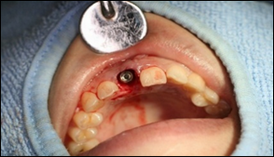

インプラントを埋入した写真です。

写真から見てわかるように、出来るだけ歯ぐきを切らずにインプラントを入れています。

上の写真のように歯ぐきをはがずにインプラントを埋入することをフラップレスといいます。

当院ではできるだけフラップレスを行っています。

仮歯をつけるための土台です。